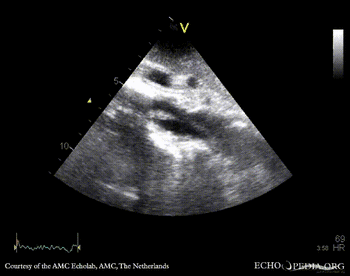

Mobile structure in abdominal aorta

Subcostal view: mobile structure (thrombus) in abdominal aorta Subcostal view: mobile structure (thrombus) in abdominal aorta

Subcostal view: mobile structure (thrombus) in abdominal aorta